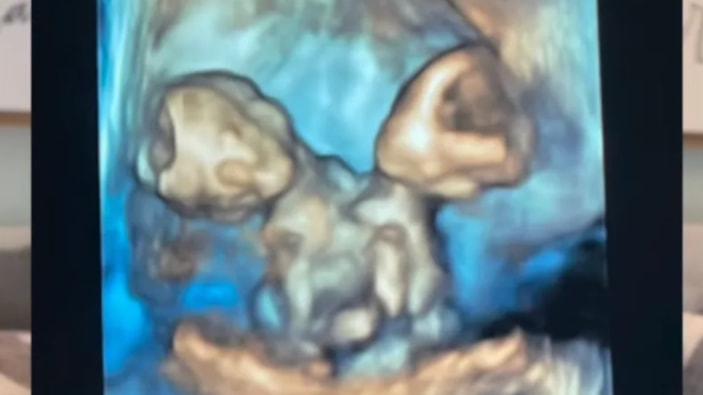

Gebeliğin yedinci haftasında yapılan kontrolde, ultrasonda yalnızca bir kalp atışı duyulmasına rağmen ikiz gebelik şüphesi ortaya çıktı.

Anne adayı, aynı kalbi, karaciğeri, bağırsakları, diyaframı ve göbek kordonunu paylaşan ikiz kız bebeklere hamileydi.

Nicole, 32. haftada sezaryenle ikizlerini dünyaya getirdi. Maria Therese ve Rachel Clare isimleri verilen bebekler, doğum anında farklı tepkiler verdi.

"Maria yüksek sesle ağladı, Rachel ise uyuyordu. Yüzlerini görmek ve paylaştıkları bedene şahit olmak inanılmazdı" diyen anne, o anları gözyaşları içinde anlattı.